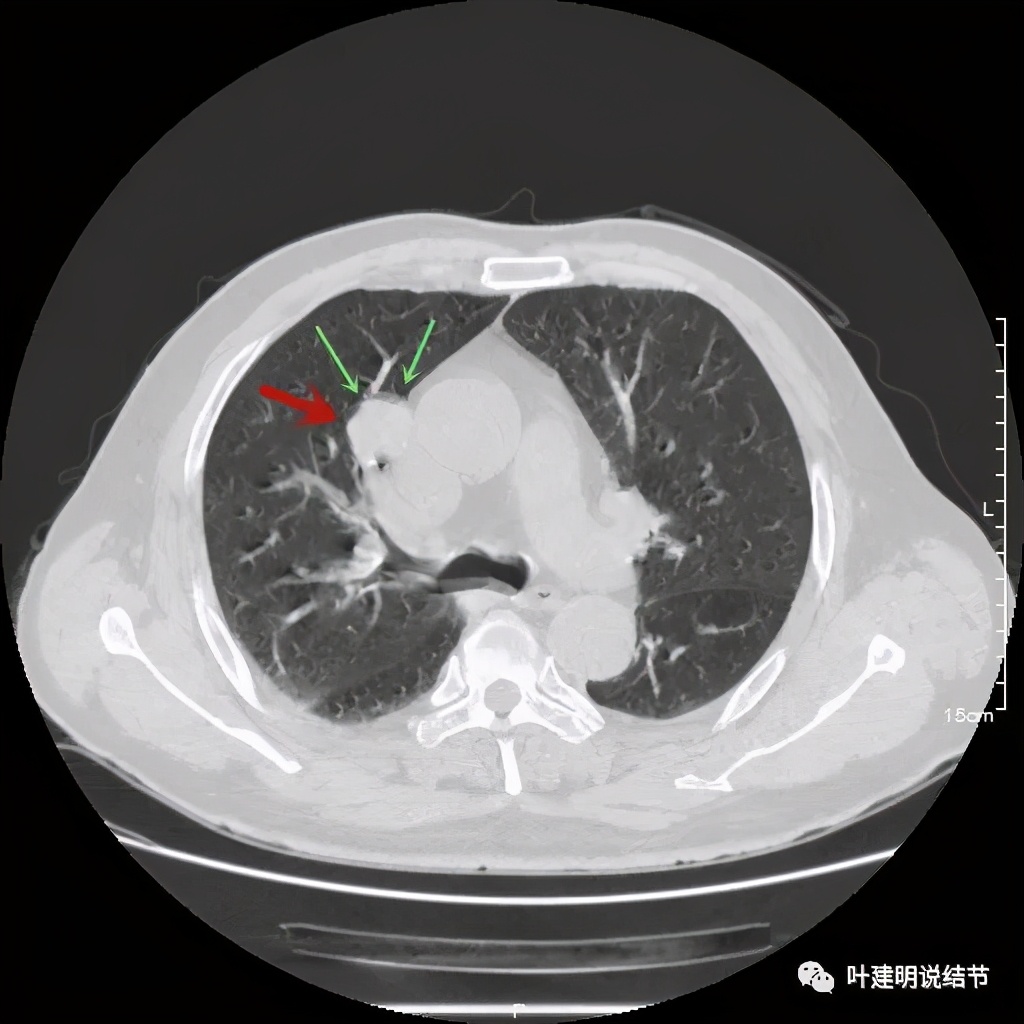

上图也示病灶密度不均,但边缘过于光滑(绿色);支气管似有截断(粉色);局部有点状钙化(蓝色)

病灶在上图层面似见支气管也是贴壁的。那么增强后又是如何呢?